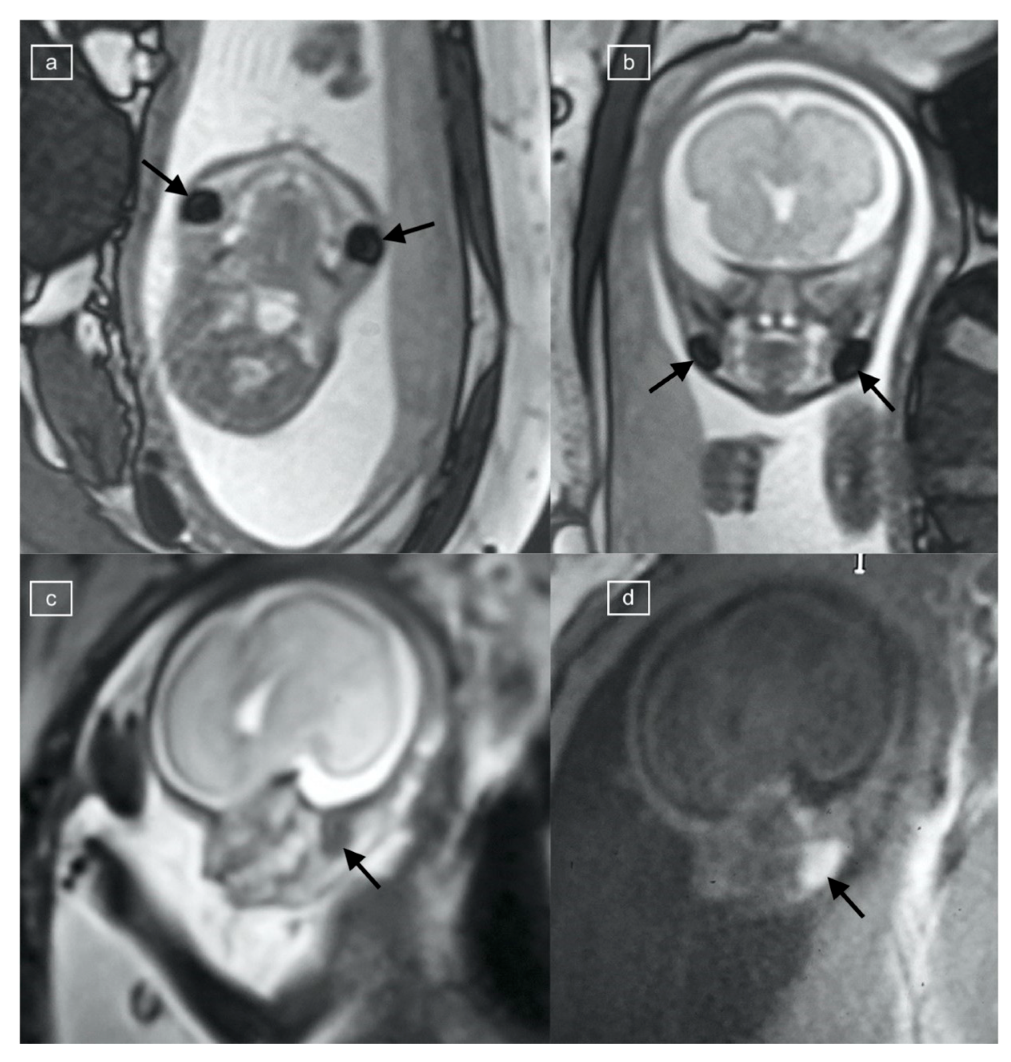

The sequences reviewed and recorded in this study included: Half Fourier Acquisition Single Shot Turbo Spin Echo (HASTE), true fast imaging with steady-state free precession (TRUFI), T1 weighted imaging (T1), echo-planar imaging (EPI), and diffusion weighted imaging (DWI). The studies were performed on a Siemens 1.5 Tesla scanner, while the 3T studies were obtained on a 3T Skyra or Prisma scanners (Siemens Healthcare, Erlangen, Germany). A positive buccal fat pad sign (BFS) (Figure 1, Figure 2, Figure 3 and Figure 4) was recorded as present if a round, symmetric, and bilateral area was seen in the submalar region of the face with the following signal characteristics: T1 hyperintensity, low signal on EPI, low signal on TRUFI, and with restriction on DWI. The signal on the T2 HASTE was recorded but not used in the definition of the buccal fat pad sign.

Figure 4. (a,b) Echo planar imaging at TE42 demonstrates low signal buccal fat pads in this 28-week gestational age fetus with diaphragmatic hernia (arrows).